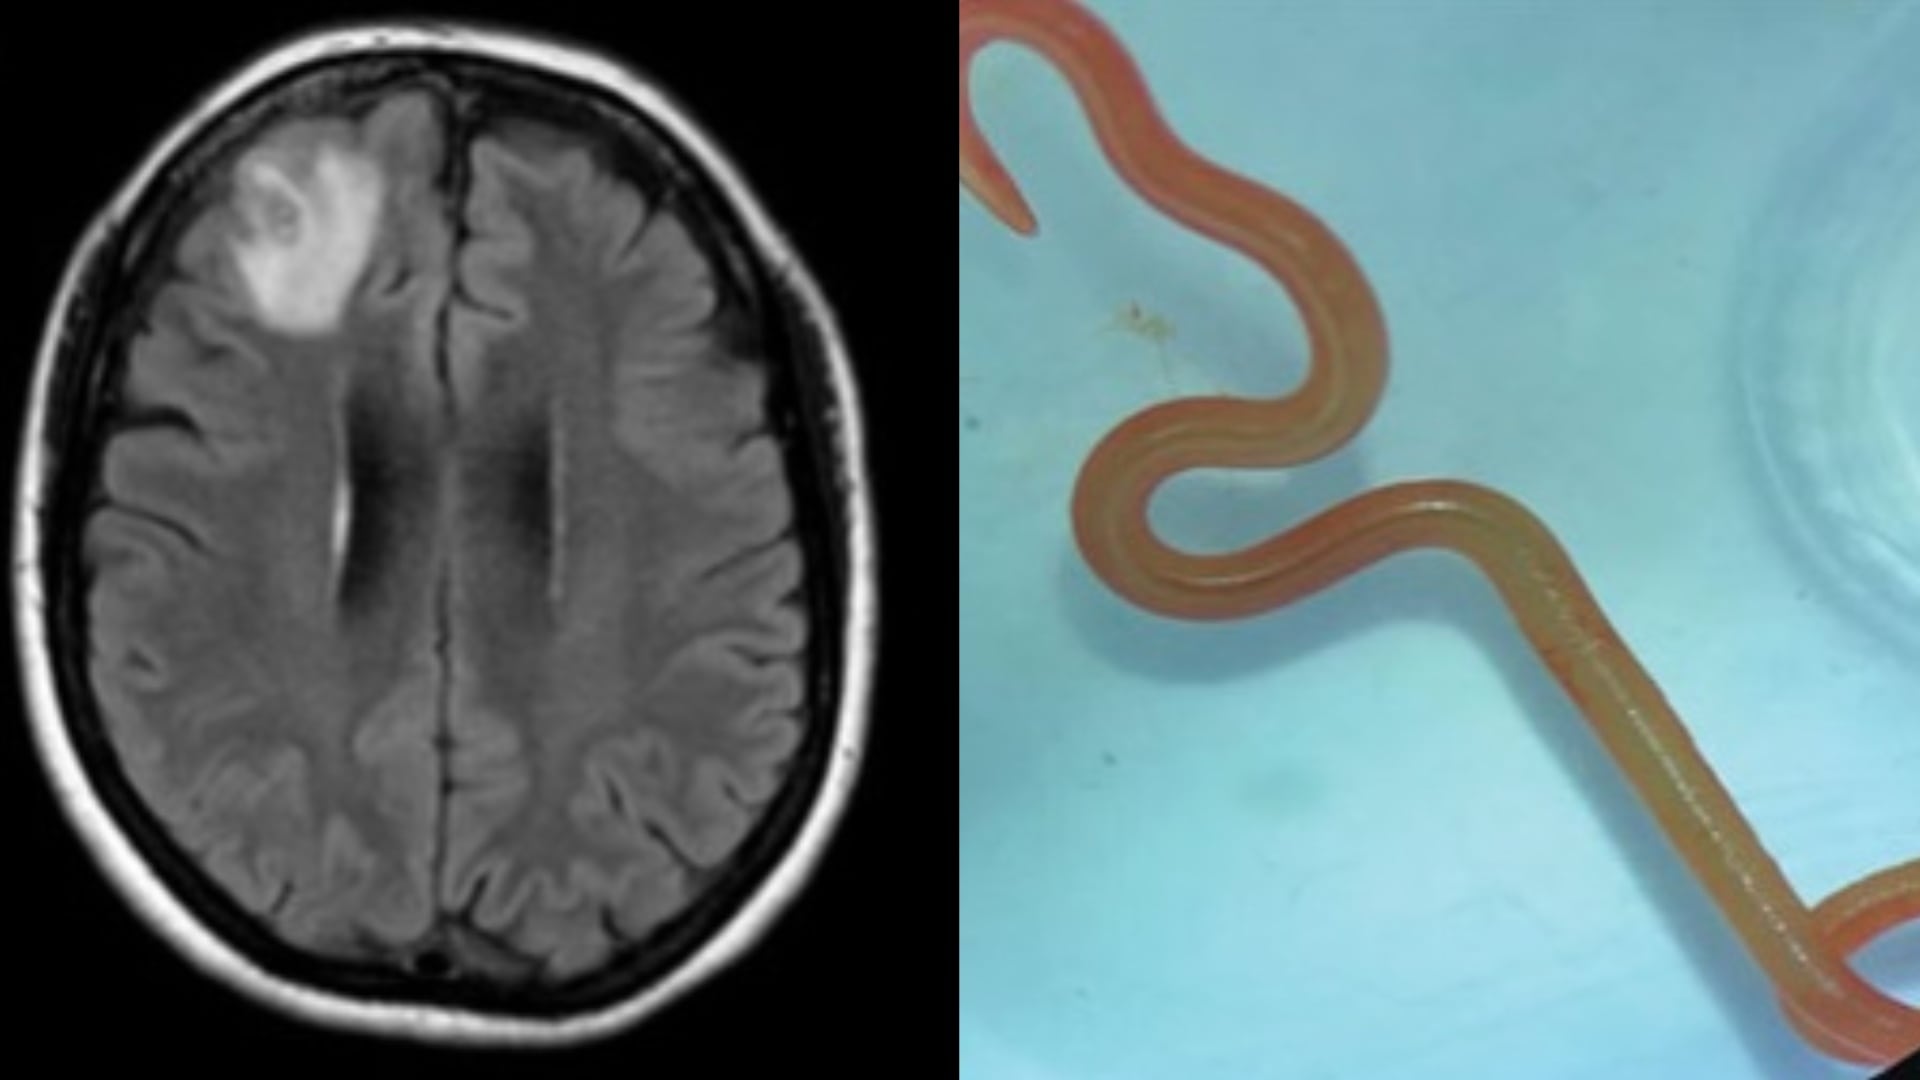

To, čo našli, však šokovalo ich aj ich. „Ó môj bože, neverili by ste, čo som práve našiel v mozgu tejto dámy – a je živý a krúti sa,“ informoval neurochirurg Hari Priya Bandi svojho kolegu z oddelenia infekčnej medicíny.

„Len sa na to pozrel a povedal: ‚Preboha, toto je Ophidascaris robertsi,‘“ spomína Senanayake.

Ophidascaris robertsi je červ, ktorý sa zvyčajne vyskytuje v telách pytónov kobercových. Dáma z Austrálie, v ktorej mozgu sa parazit vyskytol, je prvým zdokumentovaným prípadom výskytu v človeku v histórii.